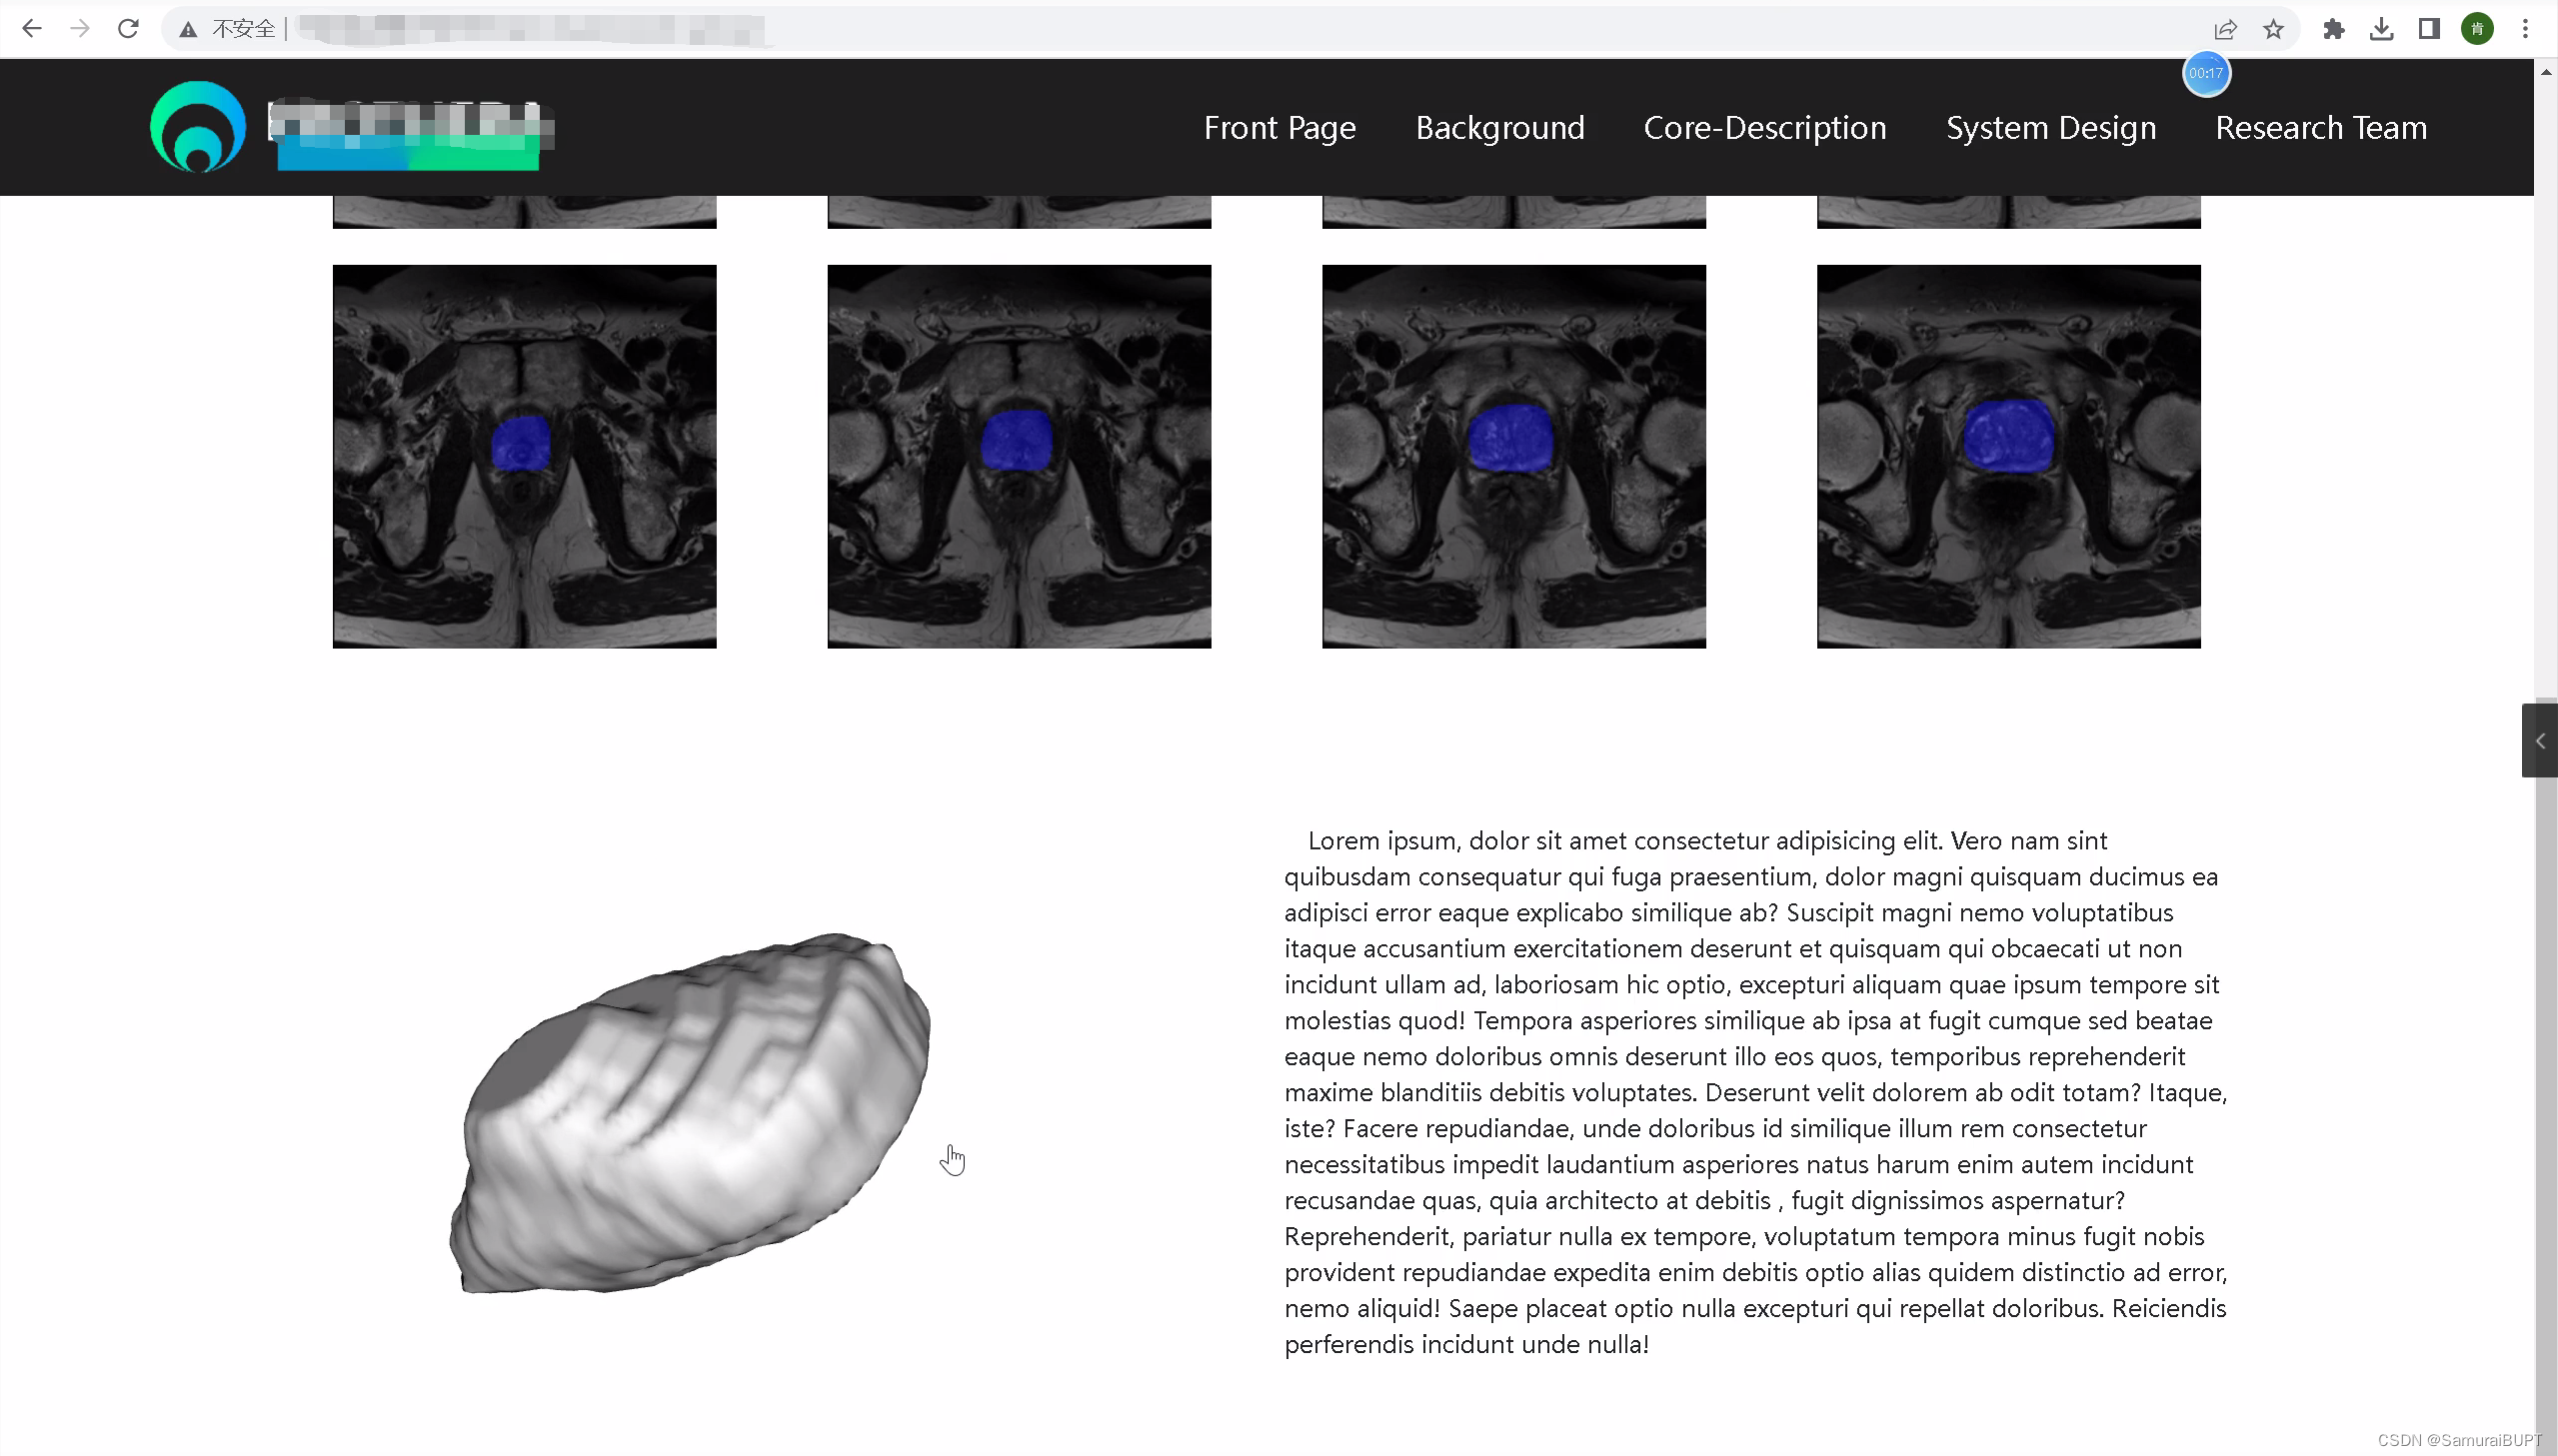

在项目的开发过程中,遇到将vtk三维重建结果放置到网页(Web Page)中进行可视化展示的棘手问题,想要实现的效果图如下:

图一:最终实现的 v t k − 3 D 模型 W e b 页面可视化 图一:最终实现的vtk-3D模型Web页面可视化 图一:最终实现的vtk−3D模型Web页面可视化